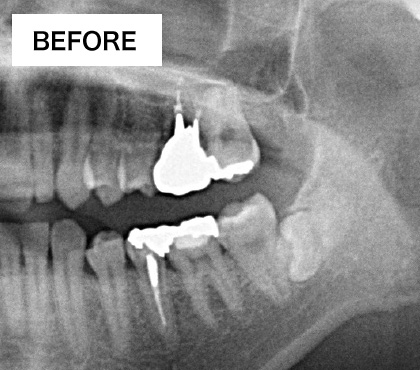

BEFORE・AFTER

奥歯へのインプラント

歯槽骨が吸収し、上顎洞が下がっています。このままではインプラントが突き抜けてしまうためインプラントはできません。

上顎洞が上に押し上げられ、インプラントを埋入するスペースができました。骨の材料も充填されているのでインプラントは安定します。